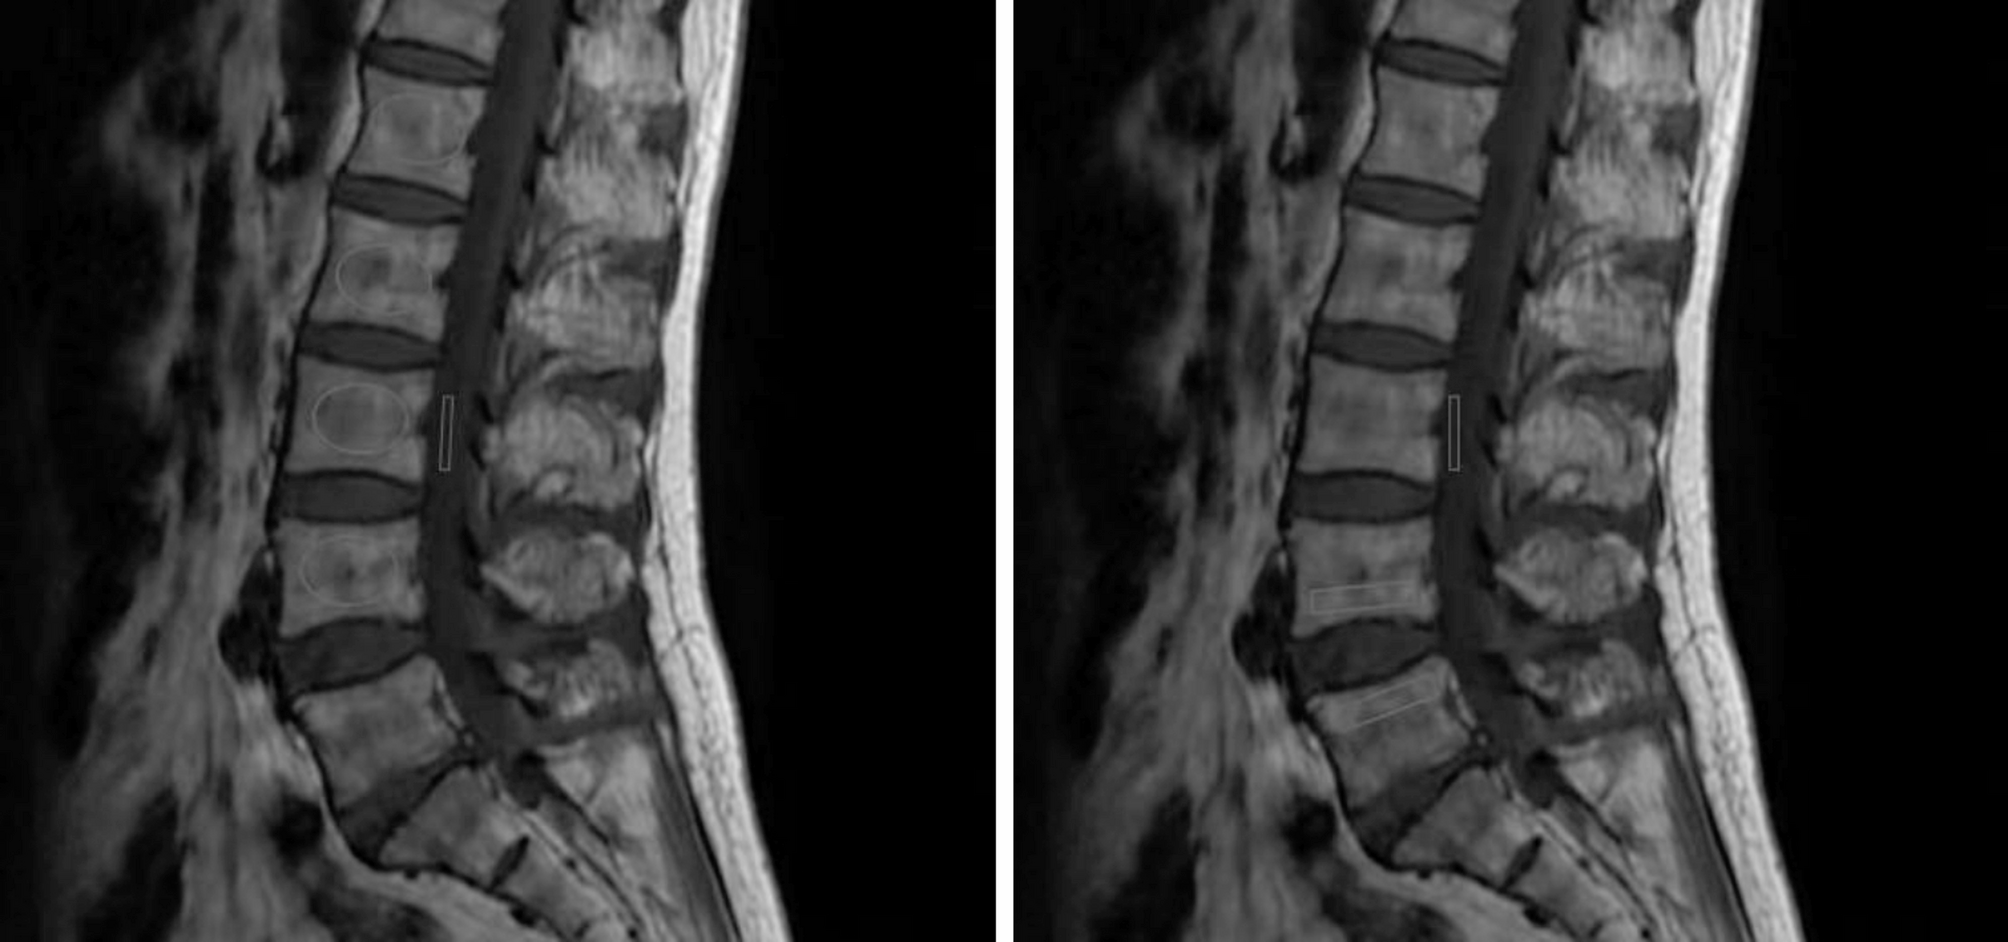

Fig.2 | Scientific Reports